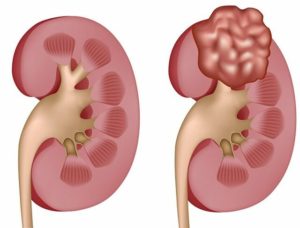

Кисты чаще диагностируются у мужчин. Представляют собой один или несколько пузырей, наполненных жидкостью, размерами от 0,1 сантиметра в диаметре и более.